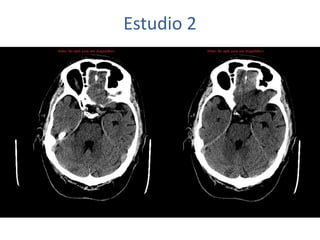

Estudio 2

• Estudio sin y con contraste, con reconstrucciones sagitales y coronales

del estudio con contraste.

Se observa una lesión ocupante de espacio en lóbulo frontal derecho que

presenta un tamaño de 18 x 32 x 22 mm (cc x ap x tr), bilobulada, no del

todo bien delimitada, con realce en anillo irregular, con hipocaptación

central, probablemente por necrosis, y asociada a un extenso edema

vasogénico con efecto masa tanto sobre los surcos de la convexidad

como sobre la cisterna insular, el sistema ventricular y la línea media,

esta última con un desplazamiento de 5 mm a la altura del septo

interventricular.

No se aprecian otras lesiones focales intra o extraaxiales de significación

patológica.

Habría que considerar como primera posibilidad que se tratase de una

lesión metastásica, por bien un tumor primario, aunque no se puede

descartar otras opciones, sin imprescindible correlación con la clínica y

con sus antecedentes.